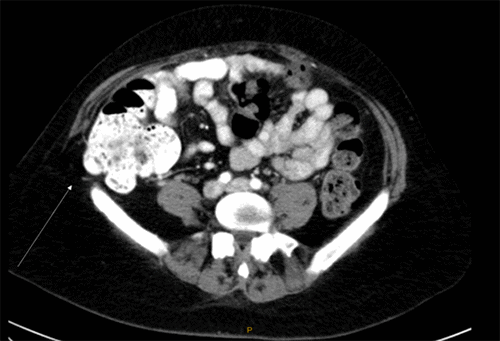

Because of the prior use of ventralex failed and the patient’s desire to exercise, we elected to use Marlex mesh for this repair. During the preoperative planning for the operation, an orthopedic colleague shared his use of the FiberTak DX suture anchors for reconstructive surgery. This “tak” is constructed with a #1-FiberWire suture. Six suture anchors were placed along the iliac crest beginning at the ASIS. They were spaced 1 cm apart (Figure 2). The anchors were deployed within the standard fashion into the cortical bone with traction.

Figure 2. Iliac Crest with Successful Placement of Six Suture Anchors. Published with Permission

The Marlex mesh was then cut to a size of 6 x 8 cm to appropriately fit the defect. The mesh was first secured to the iliac crest using the wire suture attached to the anchors (Figure 3). The mesh was then placed deep to the transversus abdominus muscle in the retroperitoneal space. The free edge of the mesh was secured to the native lateral abdominal wall musculature with interrupted #0-Prolene vertical mattress sutures. The operating table was first unflexed to 0 degrees prior to tying the Prolene sutures. This allowed for minimal tension on the mesh (Figure 4). Two Jackson-Pratt (JP) drains were placed into the subcutaneous space to prevent seroma formation.

Figure 3. Mesh Fixation to Iliac Crest. Published with Permission

Wire sutures emanating from mesh anchors are used to secure the mesh to the superior aspect of the iliac crest